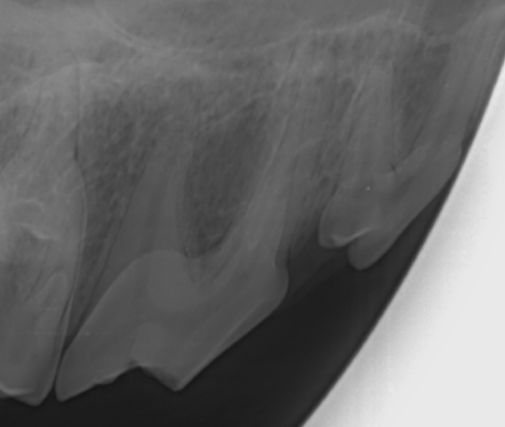

1.歯科用レントゲン検査

全身麻酔下にて口腔内レントゲン検査を行います。